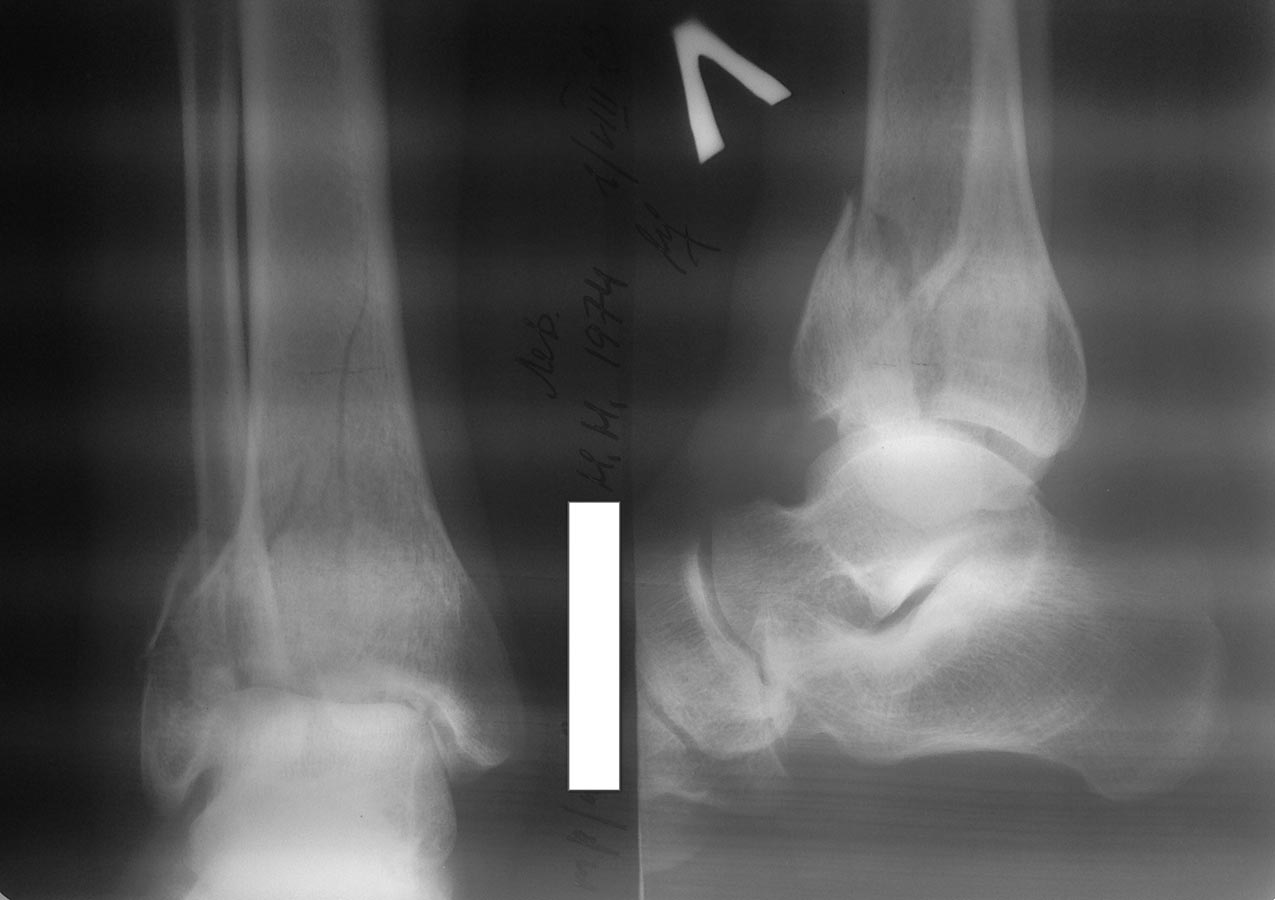

Больной 1974 года рождения, мужчина. Обстоятельство травмы: падение с

высоты 2-ух метров. В настоящее время наложены гипсовые лонгеты на обе

нижние конечности, отек умеренный, единичные фликтены.

Чувствительность и движения в пальцах стоп в норме.

Из вредных привычек - курение (более 20 лет)...